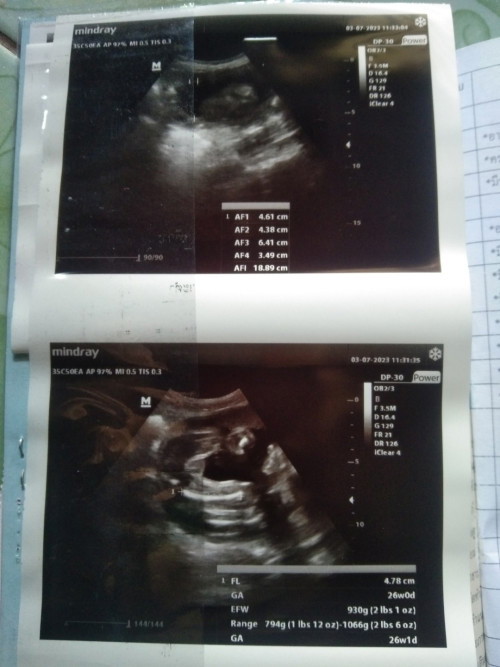

คือบ้านนี้ไปซาวด์มาค่ะ คุณหมอบอกว่าน่าจะได้ผู้ชาย เลยอยากเห็นภาพอัลต้าซาวด์เพศลูกของแม่ๆท่านอื่นค่ะ😊

บ้านนี้หมอบอกเห็นเป็นก้อนกลมๆ น่าจะผู้ชาย แต่หมอไม่ฟันธงค่ะ เพราะไม่เห็นจู๋ แม่ยังแอบลุ้นอยากให้เป็นผู้หญิงอยู่เลยค่ะ อิอิ

ล่าสุดตอน31วีคค่ะ เห็นมาตั้งแต่14วีค และน้องก็อ้าโชว์ทุกวีคเลย ไม่ให้แม่ได้ลุ้นเลยค่ะ 😅😅

รูปล่างซ้ายนะคะ หมอขยายให้เห็นได้ชัดมากน้องผู้ชายค่ะ ซาวด์ตอน30w2d ตอนนี้35wแล้วค่ะ ☺️

น้องผู้ชายค่ะ ซาวด์ตอน18Wค่ะ

ตอน 14 weeks ค่ะ ชัดเหลือเกิน

35W+2 กำหนด19สิหาคม66👶🏻💕